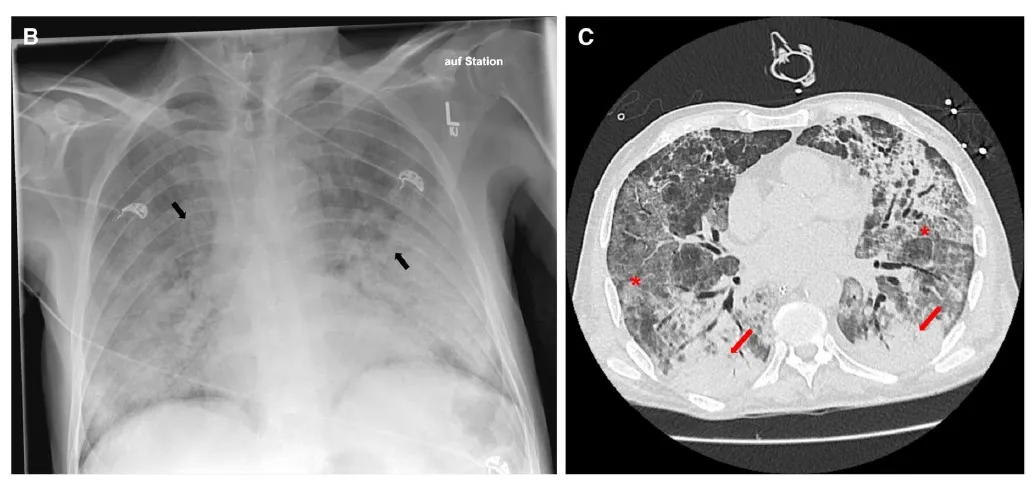

Uma causa incomum de hematúria glomerular intermitente!

Hematúria pós infecção, caso clínicos para auxiliar no entendimento de causas glomerulares comuns e raras...